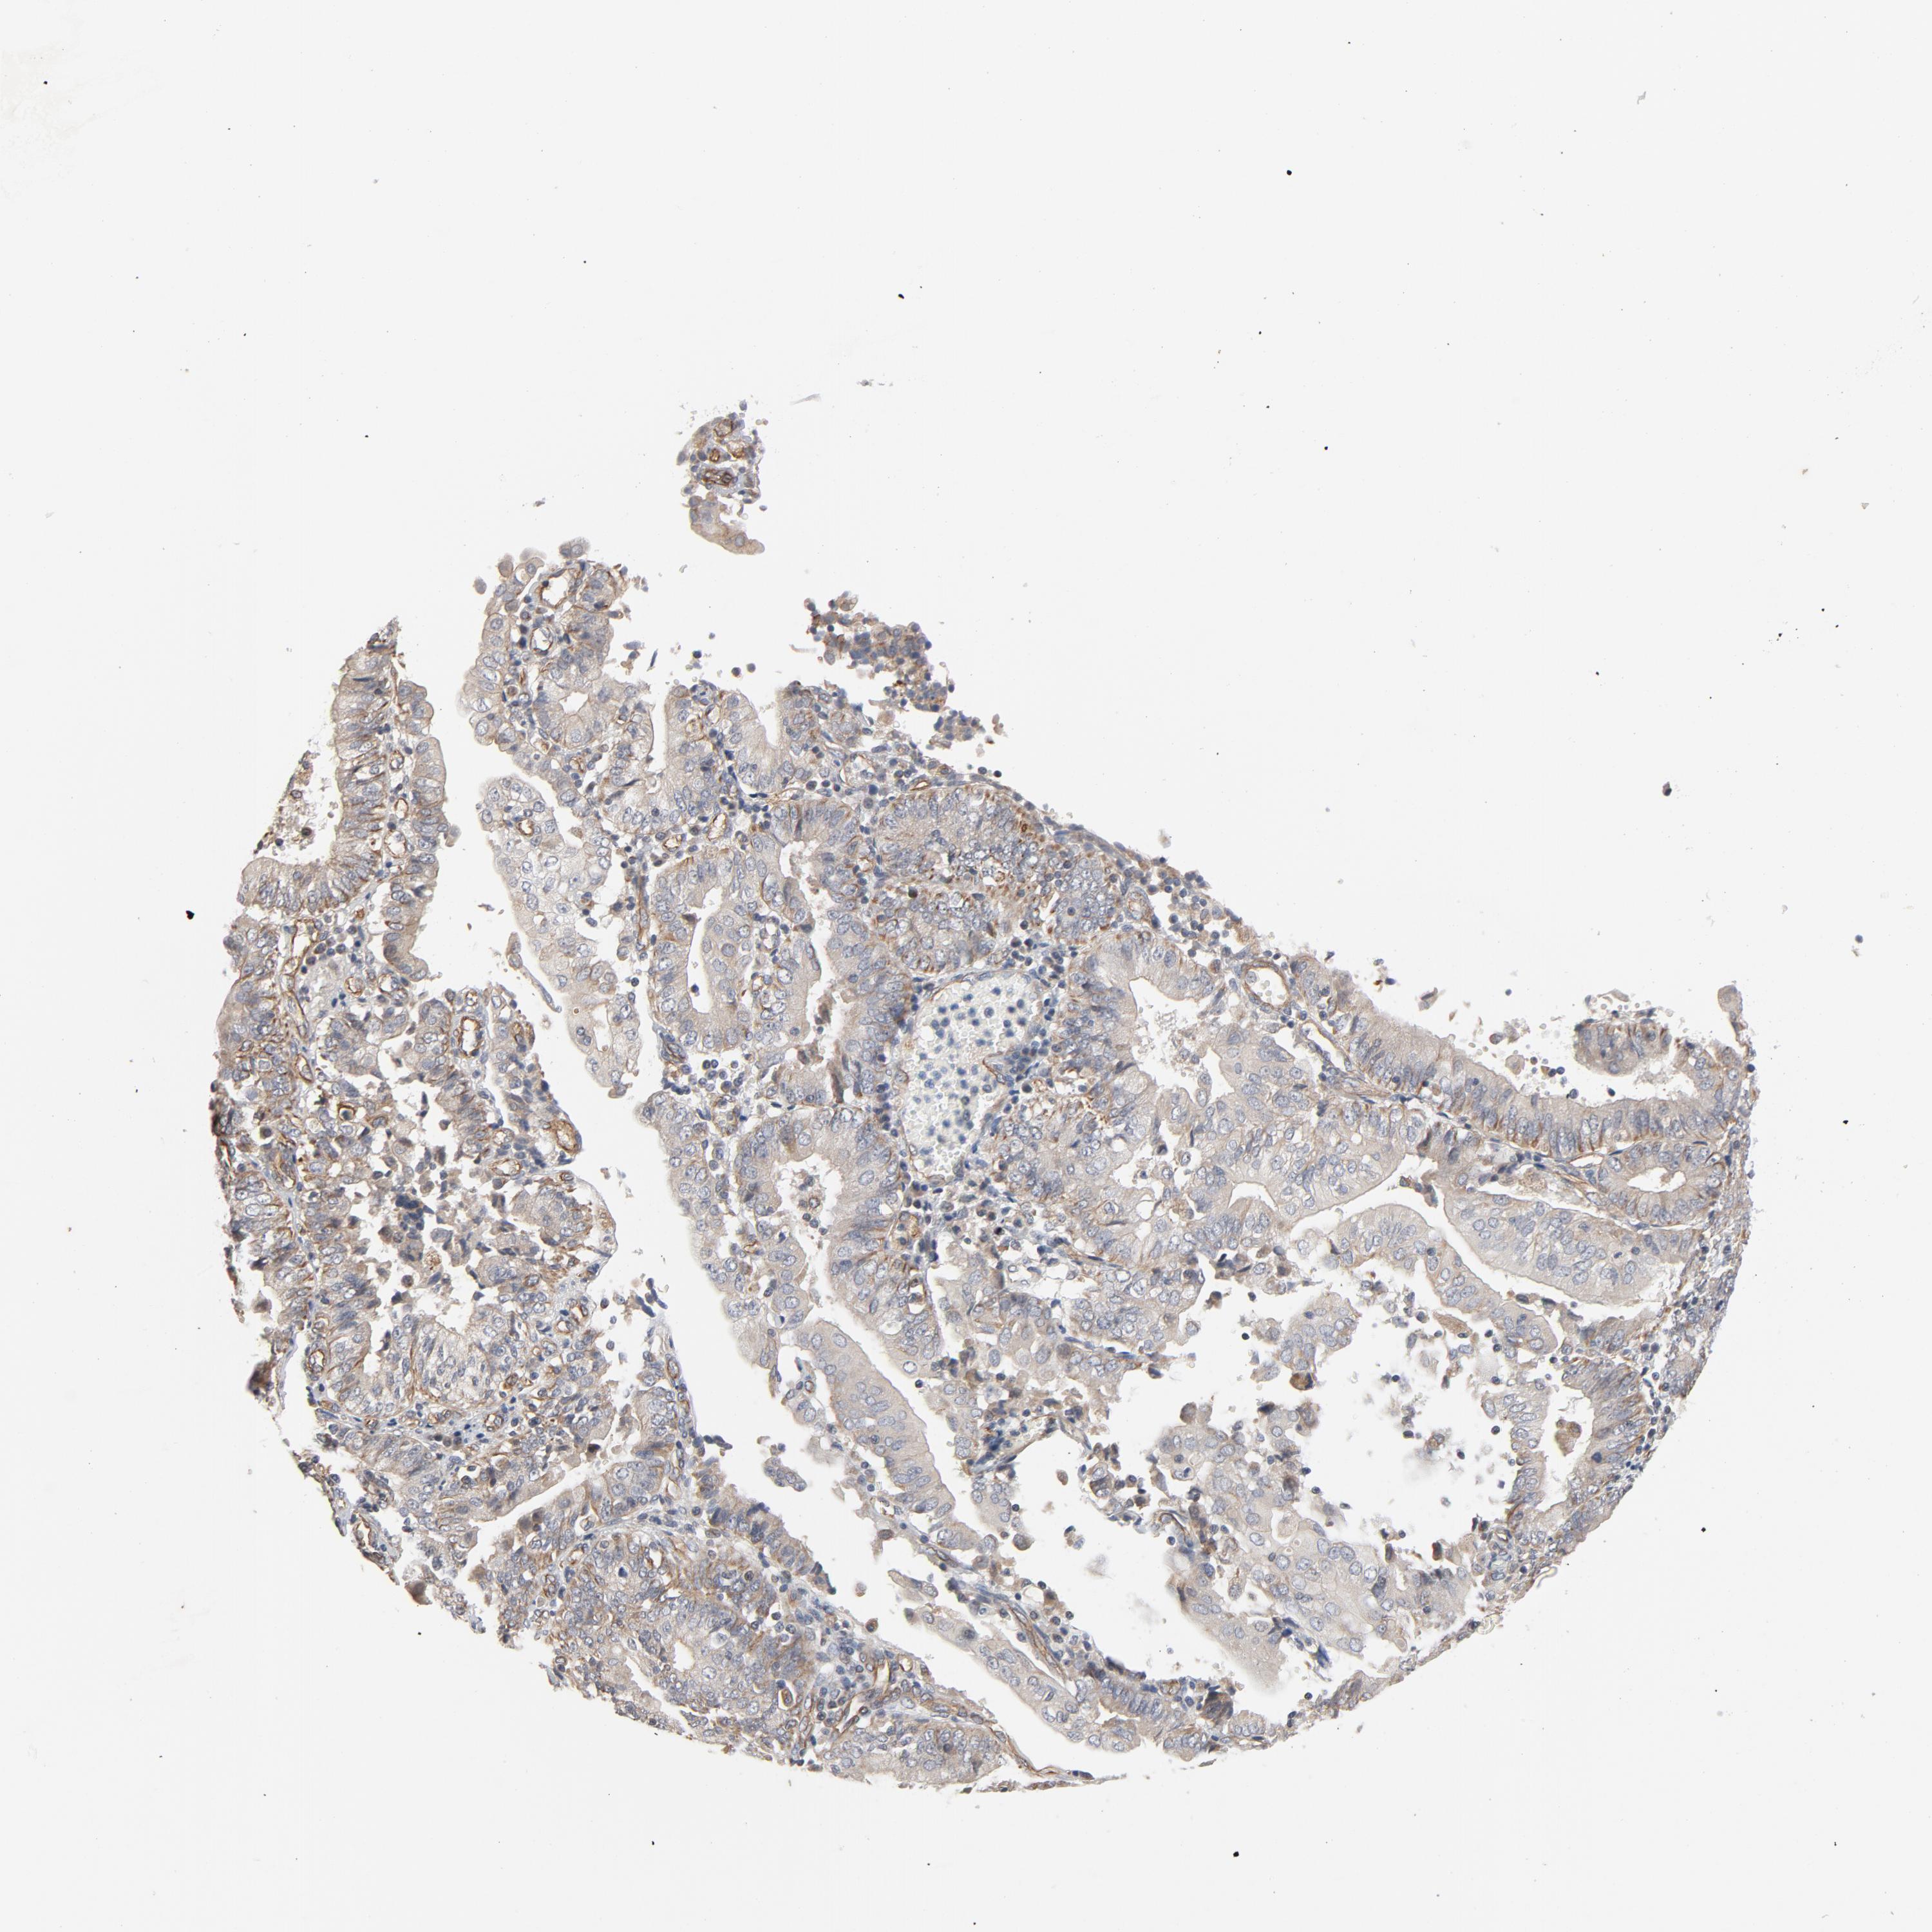

ENDOMETRIAL CANCER - Protein expressioni

A mouse-over function shows sample information and annotation data. Click on an image to view it in a full screen mode. Samples can be filtered based on level of antibody staining by selecting one or several of the following categories: high, medium, low and not detected. The assay and annotation is described here.

Note that samples used for immunohistochemistry by the Human Protein Atlas do not correspond to samples in the TCGA dataset.

Antibody stainingi

Antibody staining in the annotated cell types in the current human tissue is reported as not detected, low, medium, or high, based on conventional immunohistochemistry profiling in selected tissues. This score is based on the combination of the staining intensity and fraction of stained cells.

Each image is clickable and will lead to virtual microscopy that enables deeper exploration of all samples and also displays staining intensity scores, fraction scores and subcellular localization as well as patient and tissue information for each sample.

Antibody HPA003747

Antibody HPA019769

Staining

High

Medium

Low

Not detected

Intensity

Strong

Moderate

Weak

Negative

Quantity

>75%

75%-25%

<25%

None

Location

Nuclear

Cytoplasmic/membranous

Cytoplasmic/membranous,nuclear

Adenocarcinoma, NOS

Adenoma, NOS